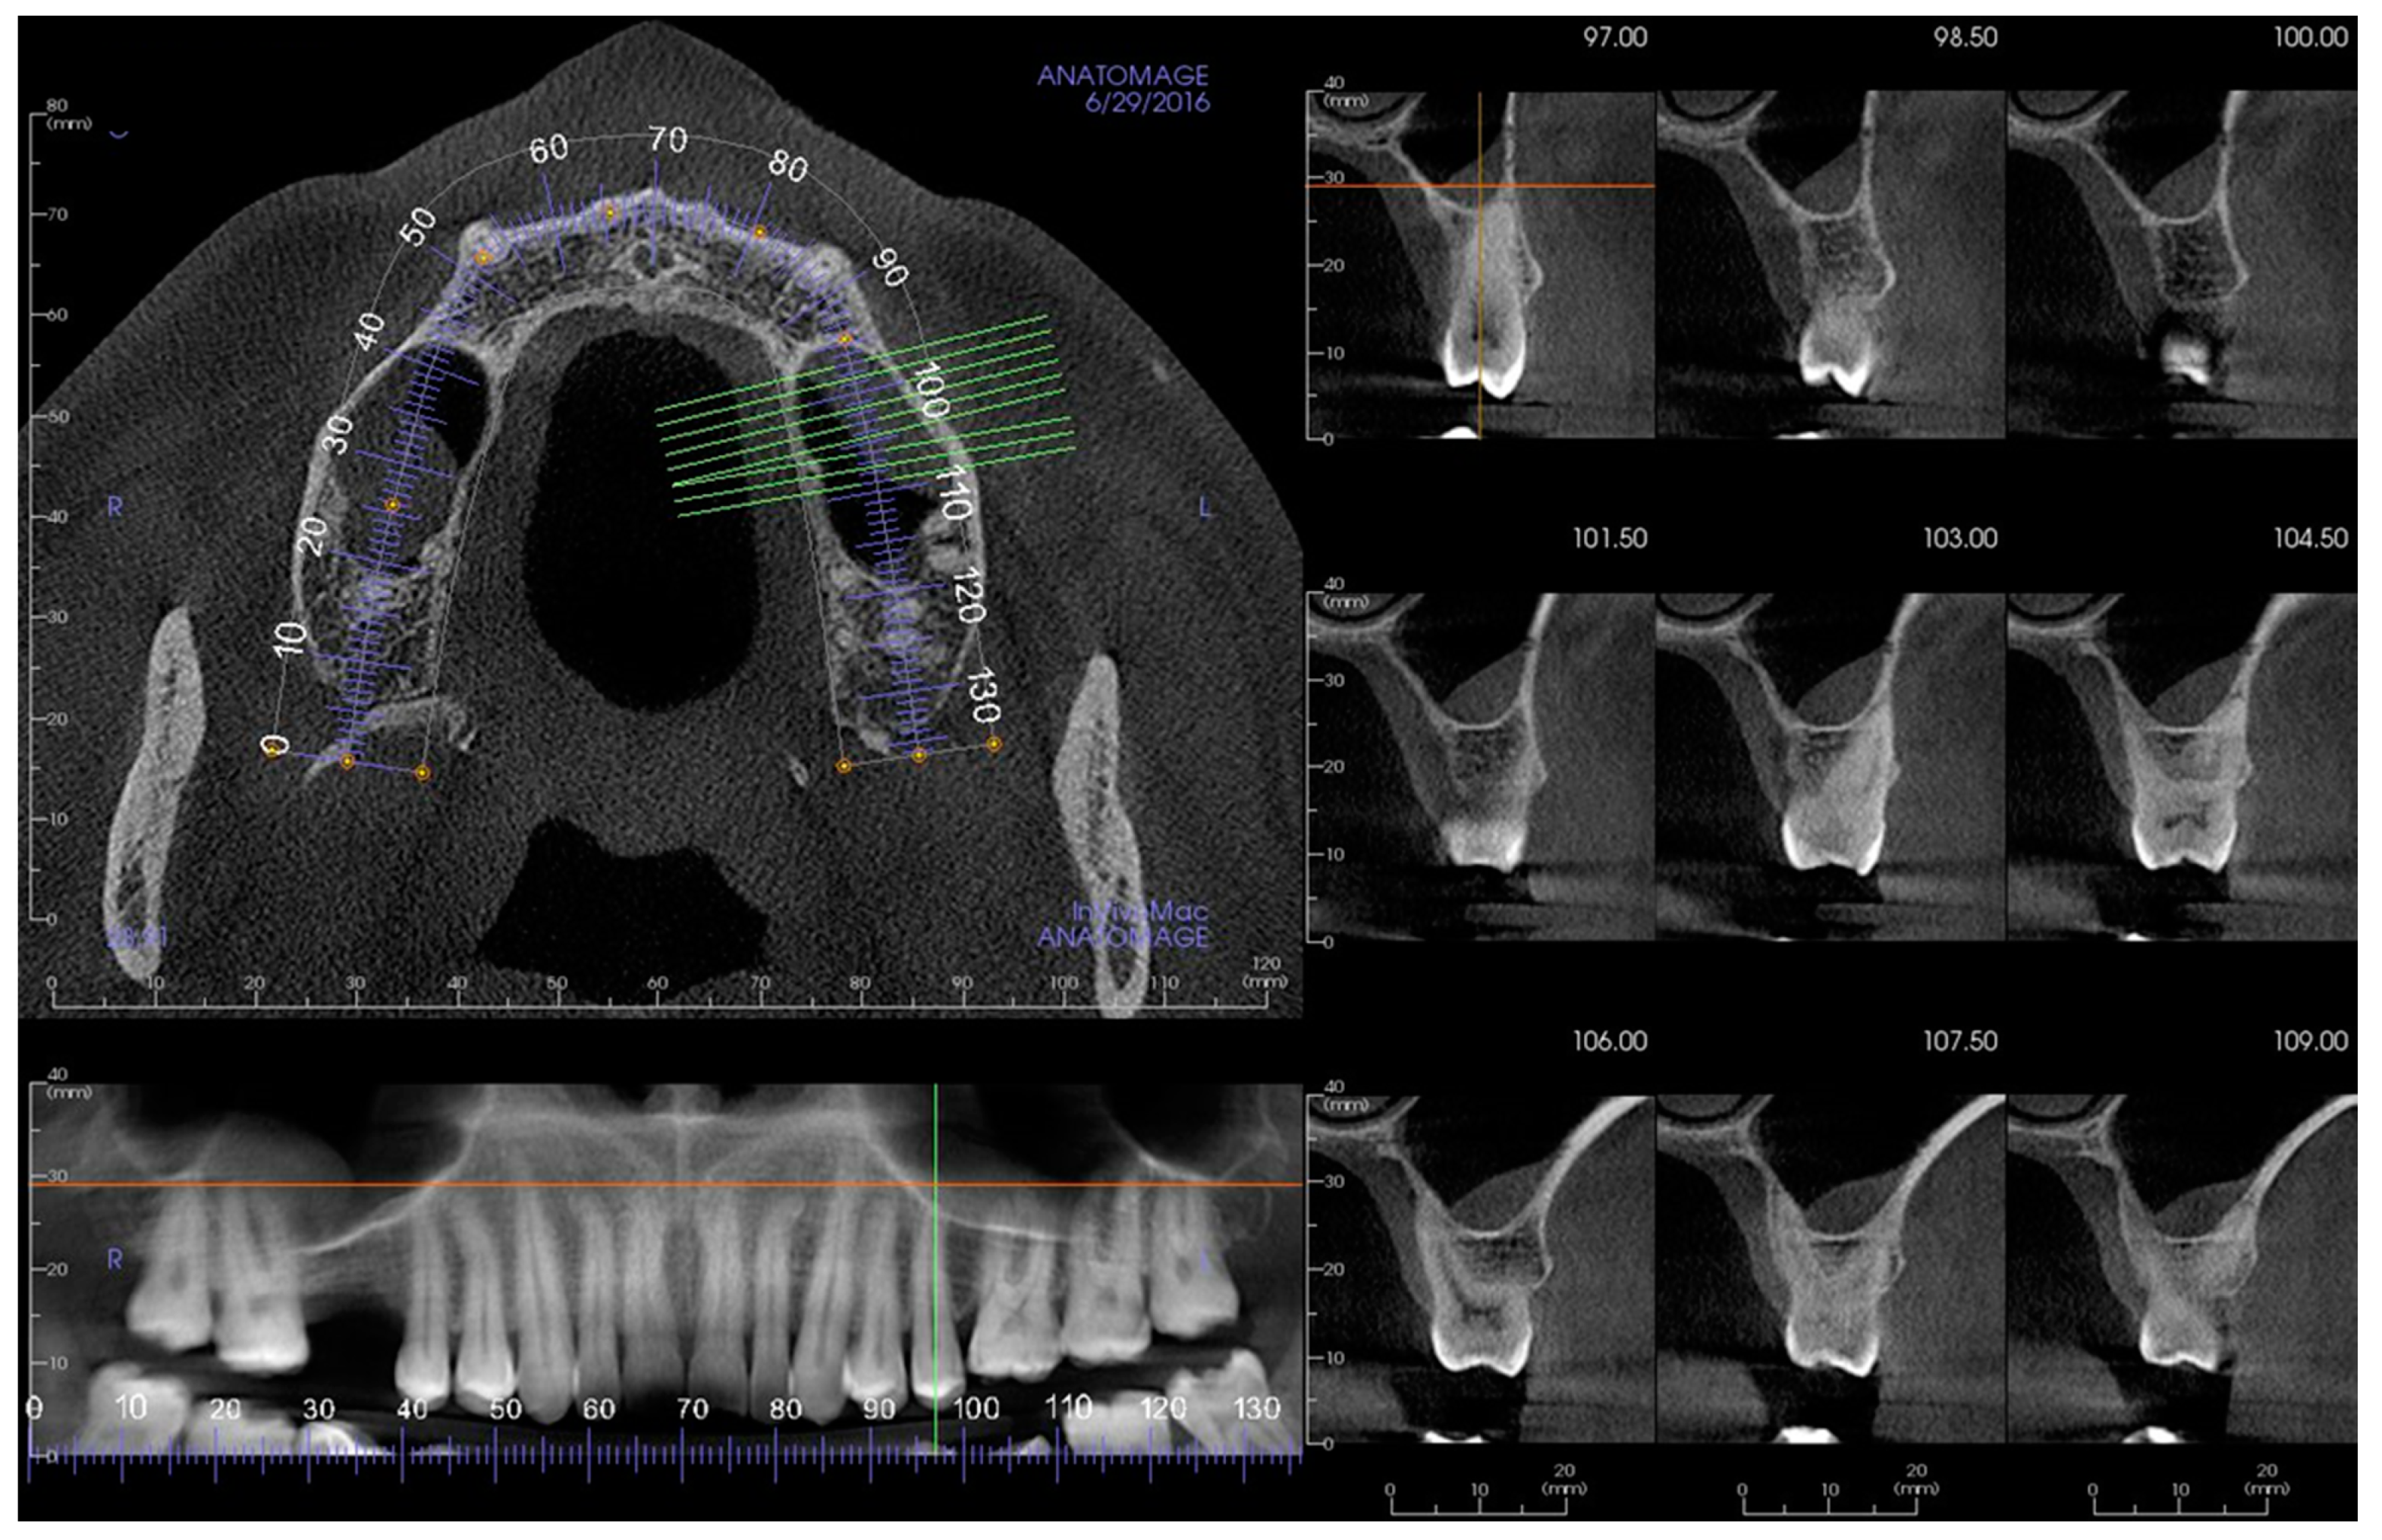

2. Materials and Methods